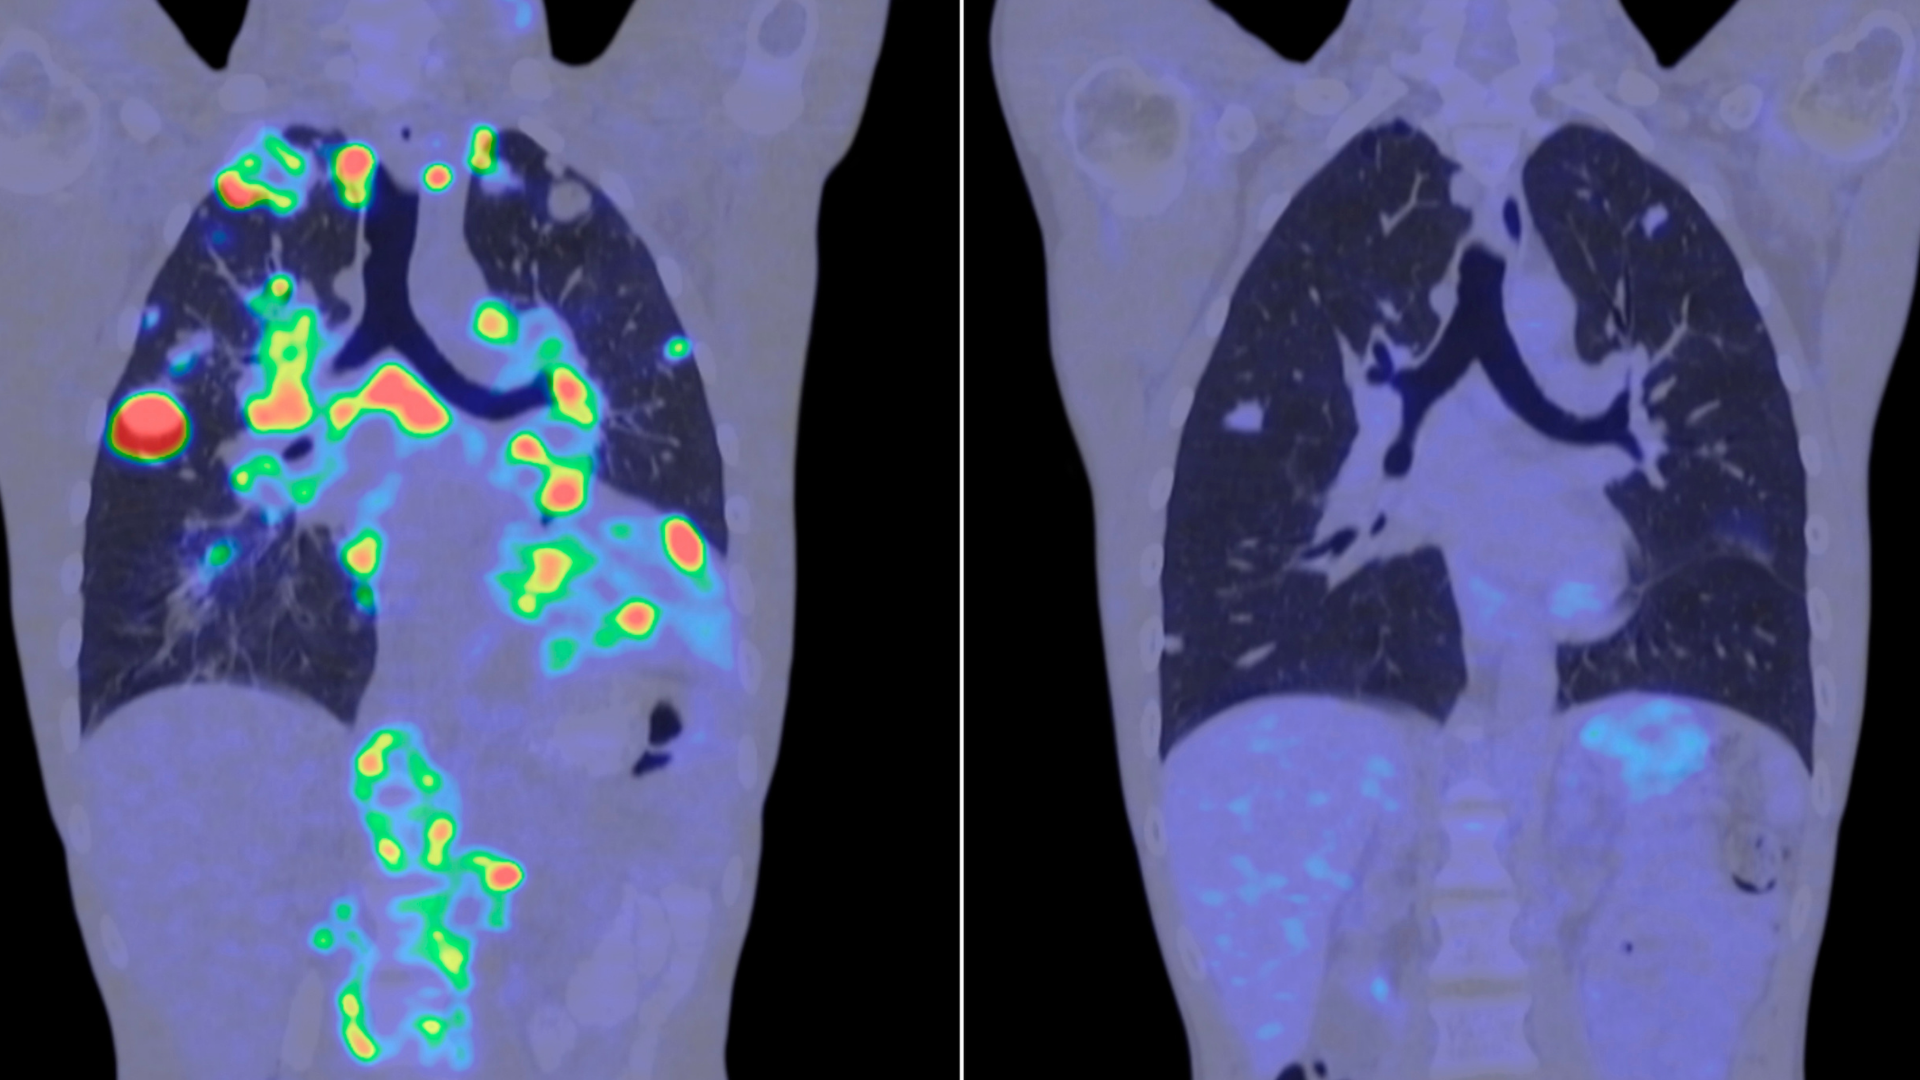

Yapay Zekâ Kanserin Erken Tanısında Nasıl Kullanılıyor?

Son yıllarda yapay zekâ destekli sistemler, kanserin erken tanı sürecinde giderek daha fazla kullanılmaya başlanmıştır. Özellikle görüntüleme yöntemlerinde elde edilen verilerin analizinde, yapay zekâ algoritmaları çok küçük ve erken dönem değişiklikleri tespit edebilme potansiyeline sahiptir.

Yapay zekâ, tek başına bir tanı yöntemi olmaktan ziyade, hekim değerlendirmesini destekleyen bir araç olarak kullanılmaktadır. Bu yaklaşım, özellikle erken evrede saptanması zor olan bazı hastalıklarda tanı sürecine katkı sağlayabilir.

Güncel çalışmalar, yapay zekâ destekli analizlerin gelecekte kanser tarama programlarının daha hassas ve kişiye özel hale gelmesinde önemli rol oynayabileceğini göstermektedir.